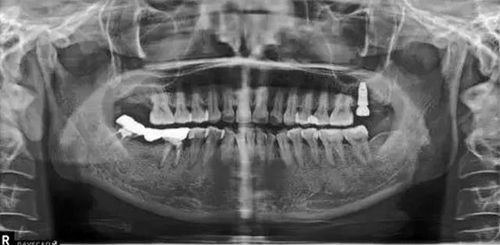

種植術(shù)后三個月復(fù)查X片??梢娮笊戏N植體已植入?;謴?fù)良好。開始著手進(jìn)行修復(fù)進(jìn)行二期手術(shù)。